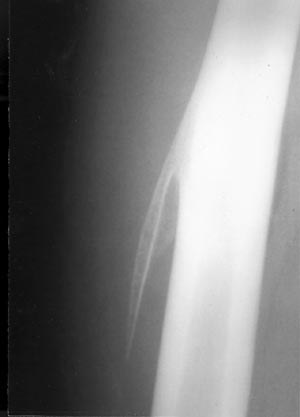

Εικόνα 1.

αιματώματος 8x8 cm). Στην απλή ακτινογραφία διαπιστώθηκε αποτιτάνωση (ως οστική

παρασχίδα) (εικόνα 1) που εκτεινόταν από το σημείο του αιματώματος, παράλληλα

προς το μηριαίο οστούν και σε μικρή απόσταση από το περιόστεο. Οι γονείς αρνήθηκαν